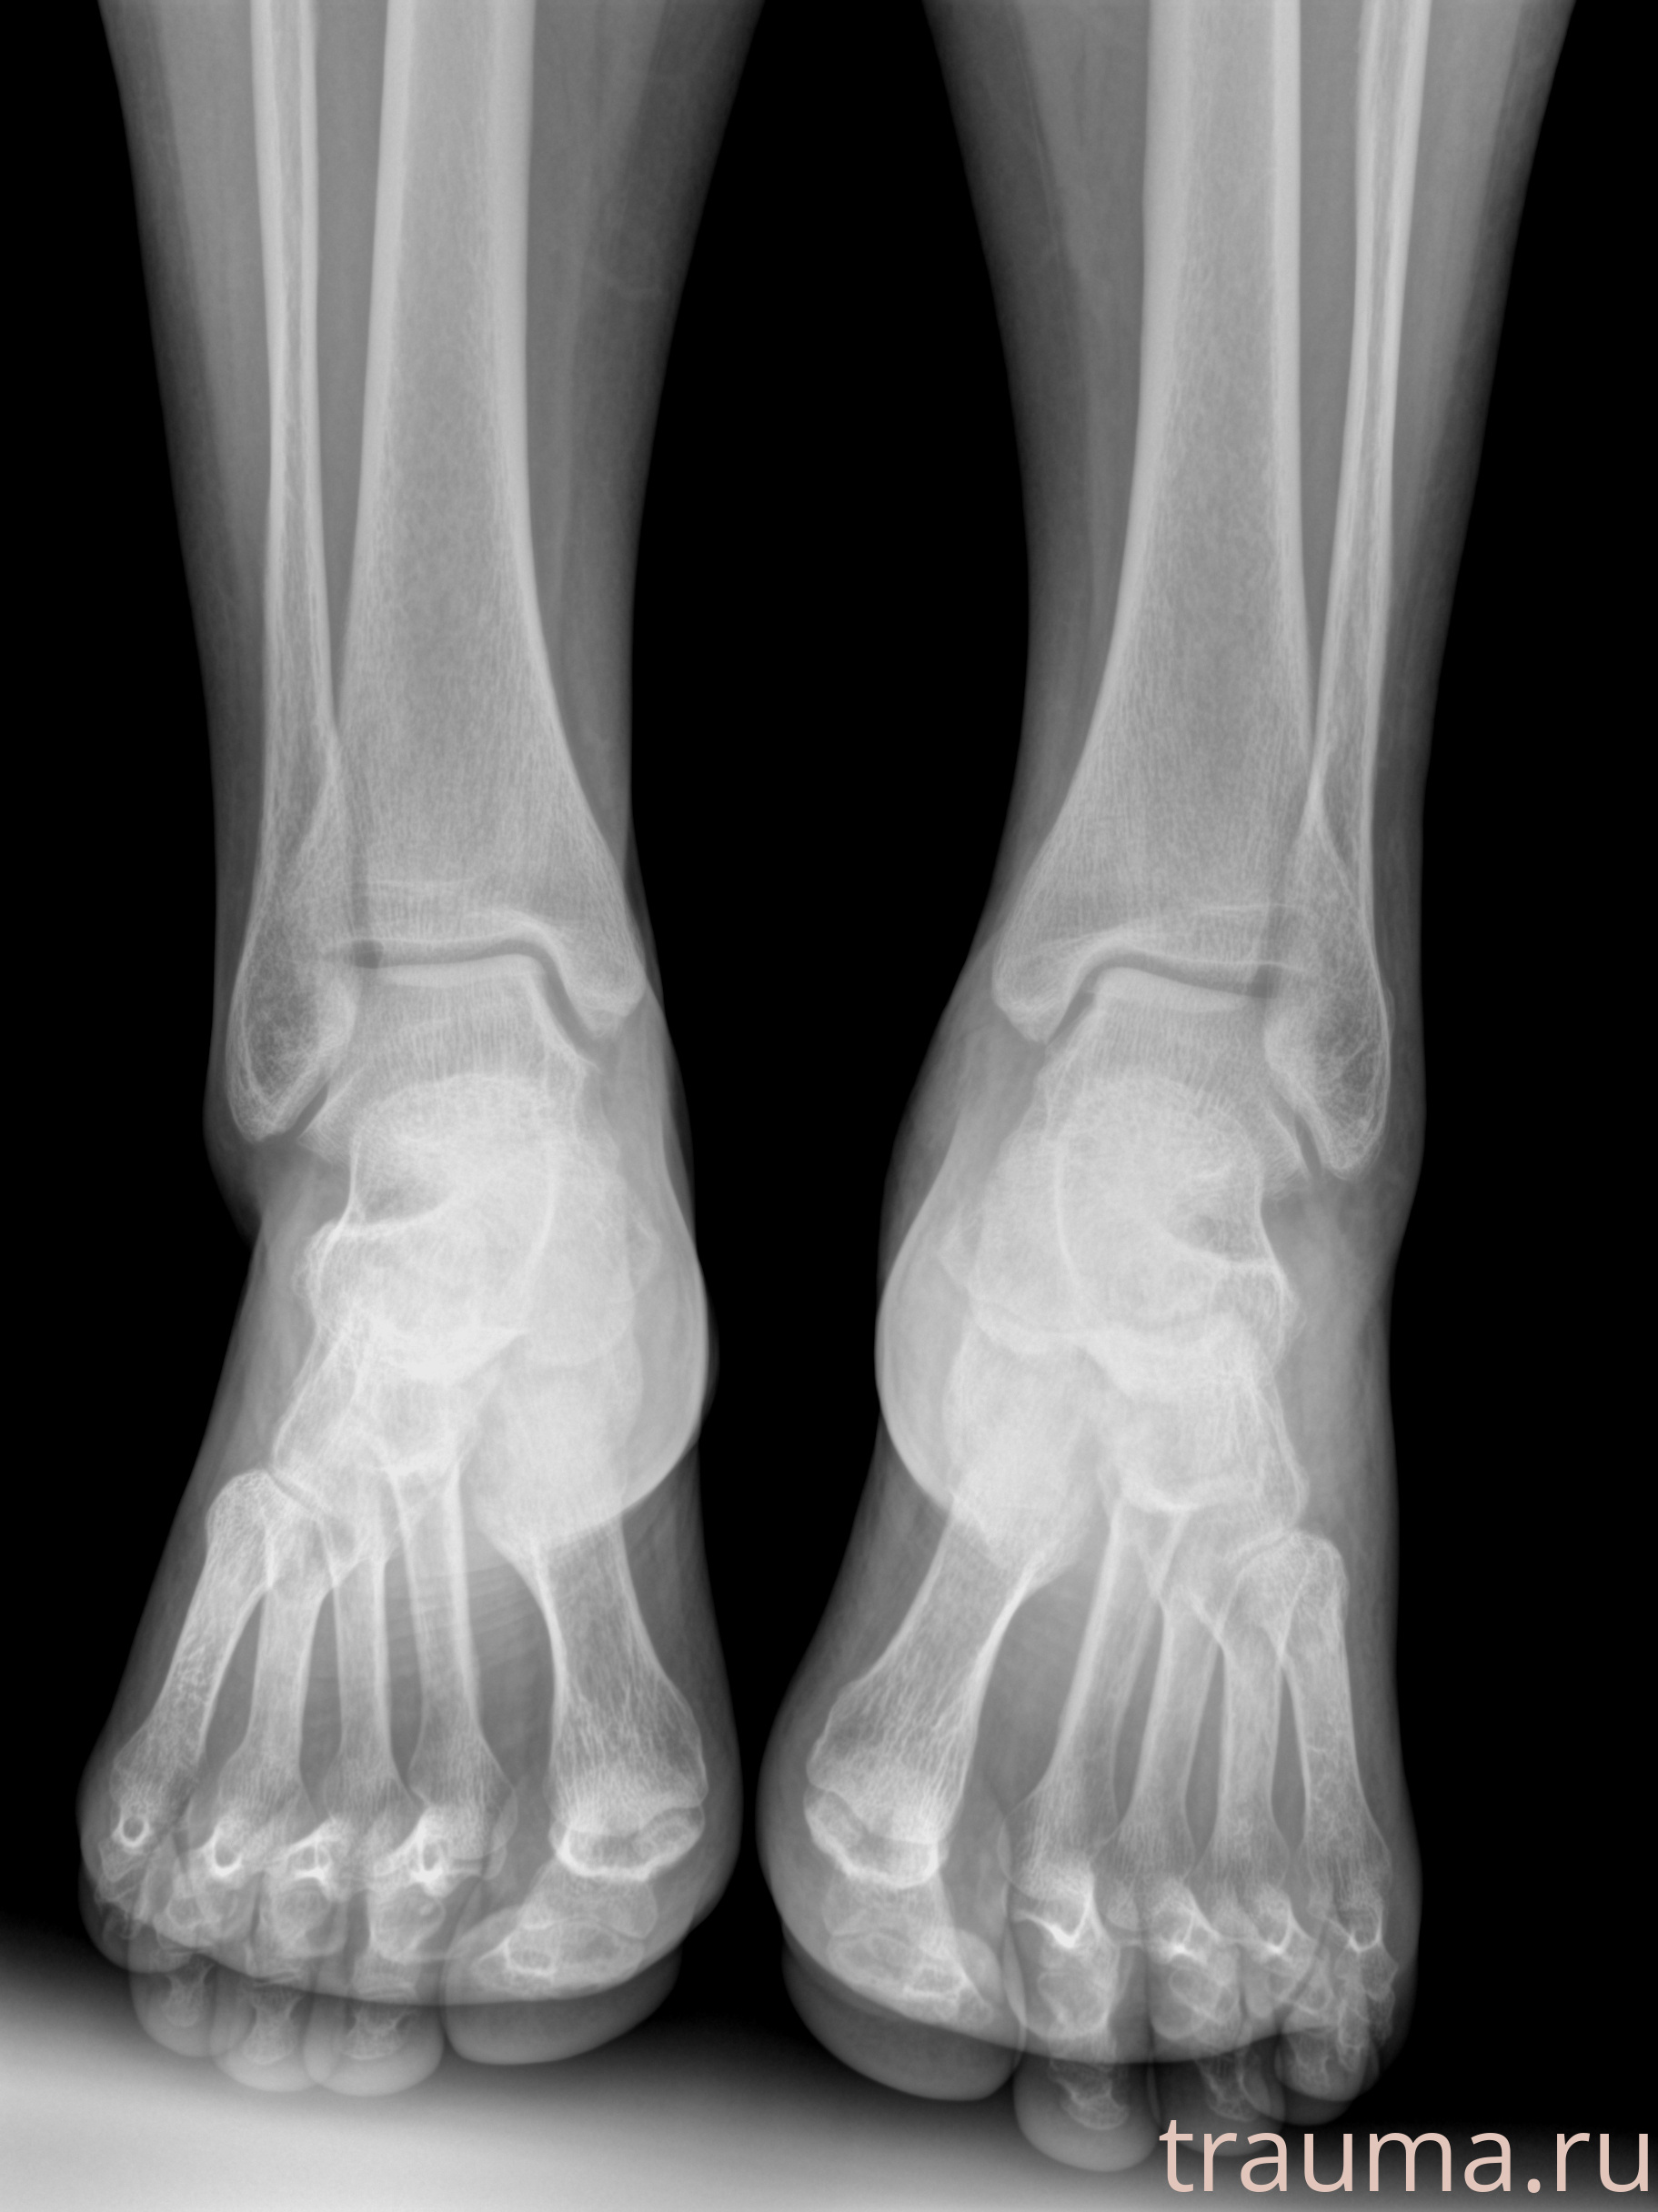

Рентгенограммы

Рентген на дому: по вашему адресу приезжает врач-рентгенолог, травматолог-ортопед с мобильным рентгеновским аппаратом, проводит диагностику травмы или заболевания, делает необходимые рентгенограммы, дает рекомендации по дальнейшему лечению. Получить качественные снимки в домашних условиях возможно благодаря уникальной методике, разработанной МосРентген Центром для института  Склифосовского